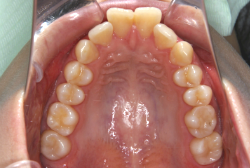

叢生(そうせい)

凸凹な歯並びのことを叢生といいます。矯正歯科に来院する患者様の主訴の中で、最も多いのが「配列の凸凹を真っ直ぐにしたい」というものです。歯の大きさと顎の大きさの調和がとれていないことが原因です。

凸凹を主体としたケースの場合、当院の平均治療期間は18ヶ月ですので、このケースは少し長めに経過しました。理由の一つは凸凹の程度がかなり重症だったと言うことですが、もう一つは、右下第2大臼歯が45度くらい前傾していたため、それを整直化させるために時間を要したと考えています。いずれにしても最終結果は大変よい状態と思います。

治療前は並びが乱れて見た目が悪いというのはもちろん問題ですが、歯科医学的に一番困るのは噛み合わせが悪いという点です。上下の犬歯(3番目の歯)は、上下的に離れた位置にあるため接触することができません。つまり歯としては存在していても、歯としては機能していないということです。